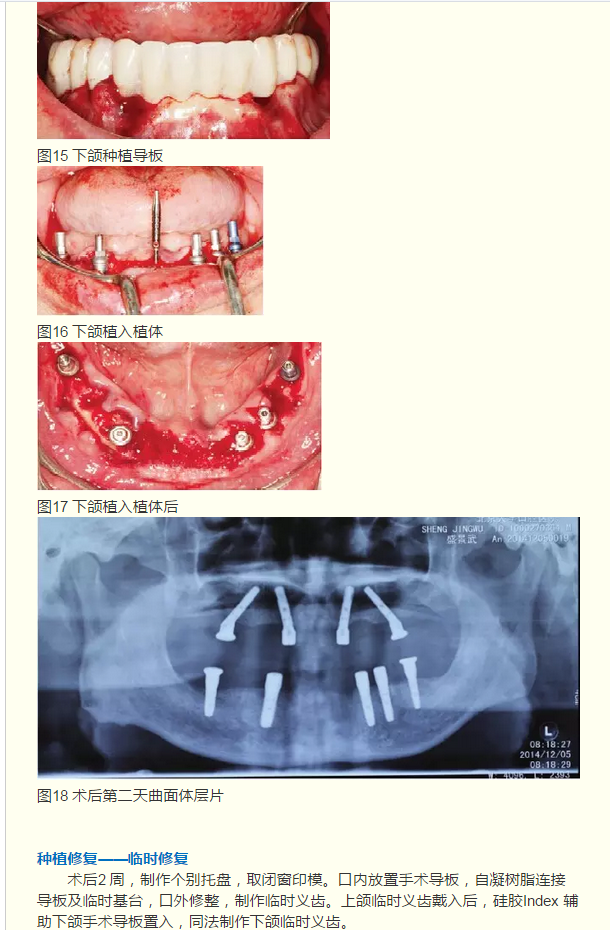

2015 BITC金獎(jiǎng)病例是如何煉成的!